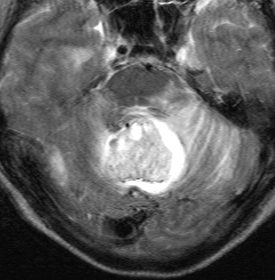

簡単な手術となる例

左右の写真は異なった患者さんのものです。両者ともに,大きな嚢胞(水たまり)を伴う小脳内部の小さな血管芽腫です。右の方に小さく白い塊(黄色の矢印)が見えるのですが,それだけが腫瘍で,濃い灰色に見える部分はのう胞といって液体がたまっているだけです。

これはとても(といっては何ですが比較的に)簡単な手術例です。小脳失調によるふらつきや水頭症よる頭痛と嘔吐などを出しますが,手術後に症状は改善します。

一般に小脳半球という場所にできたものは大きくても手術の成功率はとても高いです。小さいものでは場所と症状によってはガンマナイフなどの放射線治療も有効なことがあります。しかし,手術で摘出できるものは摘出した方が確実に治ります。